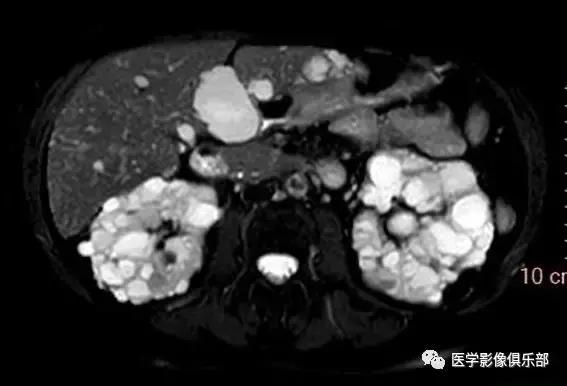

[典型病例一]:60岁,女性患者,肾功能损害。

双侧肾脏体积增大,皮质及髓质内能够看到多发大小不等的囊肿,大部分囊肿T1WI呈低信号,T2WI像上呈高信号,有少部分囊肿在T1WI呈高信号的复杂囊肿表现,可能由于里面含有不同时期的出血及高蛋白有关,肝脏内也可见较多数量的囊肿。